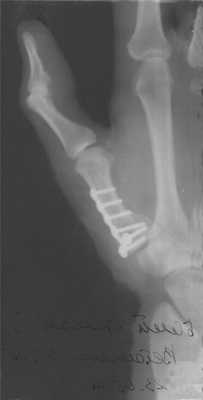

Перелом основания I пястной кости. Характерная травма для боксеров и бойцов MMA. Различают перелом Беннета — отрыв участка основания первой пястной кости, который удерживается связками, с одновременным вывихом ее большей части в запястно-пястном суставе. Перелом Роландо — многооскольчатый переломовывих I пястной кости. Обе травмы проявляются болью, деформацией и отечностью в области “анатомической табакерки” — области под основанием первого пальца — с усилением боли при движении, попытке сжать кулак. Диагностика осуществляется с учетом жалоб, данных анамнеза травмы, осмотра области повреждения и рентгенографии кисти. Лечат переломы Беннета и Роландо хирургическим путем с применением остеосинтеза — восстановления целостности кости путем фиксации отломков металлическими спицами, штифтами или пластинами.

Перелом средней части I пястной кости. Чаще возникает вследствие прямого удара по кости. Проявляется болью, отеком и деформацией в области первой пястной кости. Диагноз устанавливается с учетом жалоб пациента, сведений о механизме повреждения, осмотра области первой пястной кости и рентгенологического исследования костей кисти. Лечение — гипсовая иммобилизация сроком 4-5 недель, при смещении отломков — предварительная закрытая репозиция. При неэффективности консервативной репозиции для сопоставления отломков проводится операция — спицевой остеосинтез.

Пример операции доктора Валеева по восстановлению после перелома первой пястной кости: